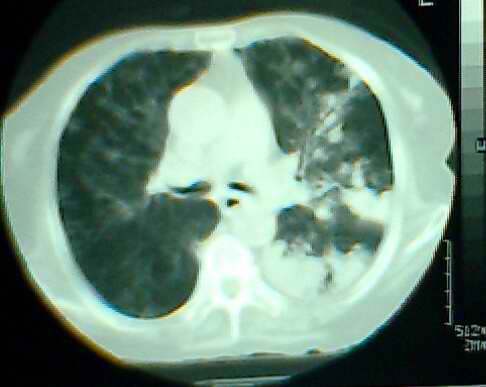

以上是2009-05-25的照片。

以下是引用hhx58在2009-9-11 19:48:00的发言:[br]有4个是心电监护的电极。[br]ct图片可见有肺气囊。但未拿到片上传。

以下是引用37度在2009-9-12 11:54:00的发言:[br][br] [br] 支气管扩张合并混合型感染 [br] [br]

以下是引用dyqct在2009-9-12 8:42:00的发言:[br]慢性支气管炎合并间质纤维化、肺气肿、支气管扩张、感染。建议ct进一步检查。

以下是引用黑白光影在2009-9-12 16:43:00的发言:[br]慢支并感染(霉菌?)